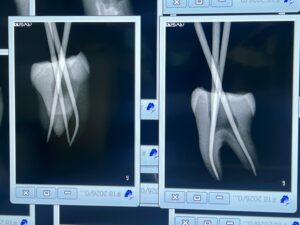

T先生

このセミナーに来て、たまたま大学の同級生のI先生と再会したT先生のテストケースは以下だ。

MB2を探索しようとしてファイルが破折したのでやり直してテストケースを3つも行ったT先生。

いやあ上手いです。

先生も保険でなく、自費で根管治療を行うべき人ですよ。